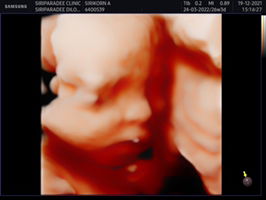

25week แล้ว สอบถามแม่ๆหน่อยค่า